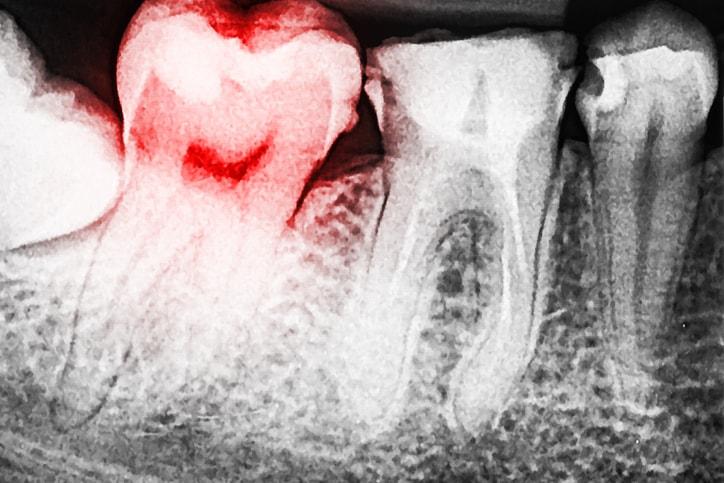

Viêm xương ổ răng là một biến chứng gây đau có thể xảy ra sau khi nhổ răng.

Sau khi bạn nhổ răng, ngay vị trí ấy sẽ hình thành cục máu đông để bảo vệ các xương cơ, các mô và dây thần kinh. Trong trường hợp bạn bị viêm xương ổ răng, cục máu đông sẽ không thể hình thành. Điều này có thể dẫn đến nhiễm trùng và khiến bạn có cảm giác đau liên tục trong 5 hoặc 6 ngày.

Khi bị viêm xương ổ răng, bạn có thể nhìn thấy nơi răng bị nhổ có mẩu xương trắng, thay vì là máu đen như bình thường. Bạn sẽ cảm thấy đau sau khoảng 2 ngày kể từ khi nhổ răng và cơn đau càng ngày càng nghiêm trọng. Tệ hơn nữa là bạn có cảm giác đau tai, hôi miệng và giảm vị giác.